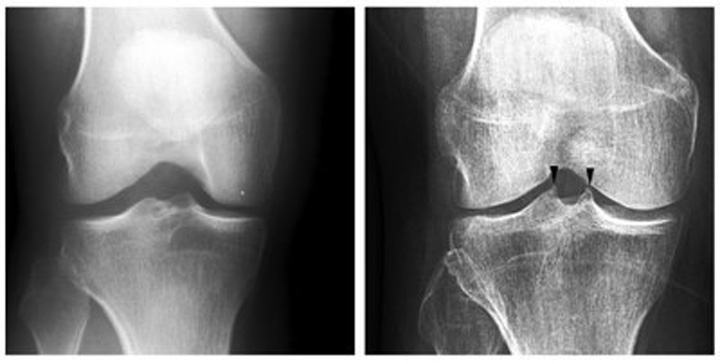

Algorytm sztucznej inteligencji przeszkolono w wykrywaniu cech radiologicznych, które mogą przewidzieć chorobę zwyrodnieniową na podstawie prześwietlenia. Chodzi o stwierdzenie, czy guzki piszczelowe w stawie kolanowym są kolczaste czy nie, gdyż może to oznaczać początek rozwoju choroby stawów. Doświadczeni lekarze potrafią to ocenić na podstawie zdjęcia rentgenowskiego, ale dzięki sztucznej inteligencji dałoby się dokonać analizy automatycznie, co pozwoliłoby znacznie przyspieszyć diagnostykę.

Do opracowania algorytmu wykorzystano około 700 zdjęć rentgenowskich, a następnie jego skuteczność zweryfikowano na podstawie 200 kolejnych prześwietleń. Modelowi udało się uzyskać skuteczność na poziomie 87%, co stanowi bardzo obiecujący wynik. Na razie jest jednak zbyt niski, aby technologię można było wykorzystać do powszechnego diagnozowania pacjentów.